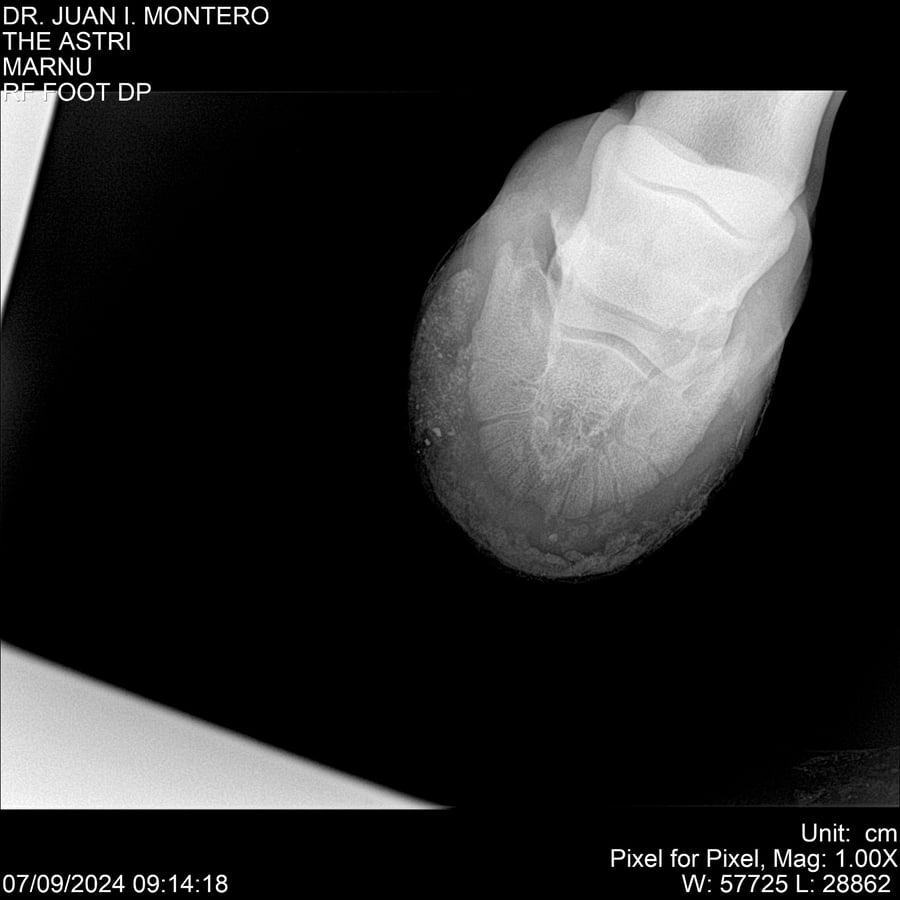

LOTE 10, THE ASTRI Lote Anterior Volver al remate Lote Siguiente Ficha Contacto Montevideo - Ficha del Lote Identificador: #282514 Categoría: Yeguarizos Montevideo - 60 Visualizaciones ClicData Contacto Empresa: Abelenda N. R., Walter Hugo Nombre*: Teléfono* : E-mail* : Mensaje Enviar Registrese gratis Este contenido Exclusivo está disponible sólo para usuarios registrados Ingresar